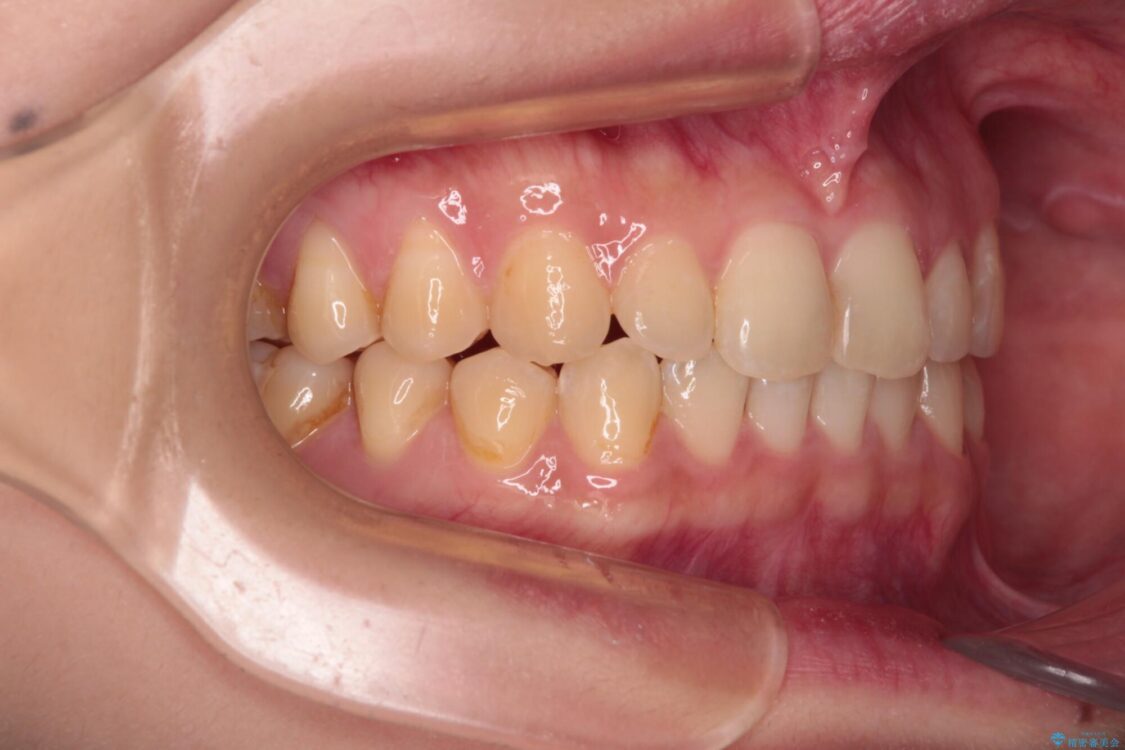

治療前

• 治療途中の奥歯と矯正治療の後戻り インビザライン・ライトによる矯正治療 治療前画像